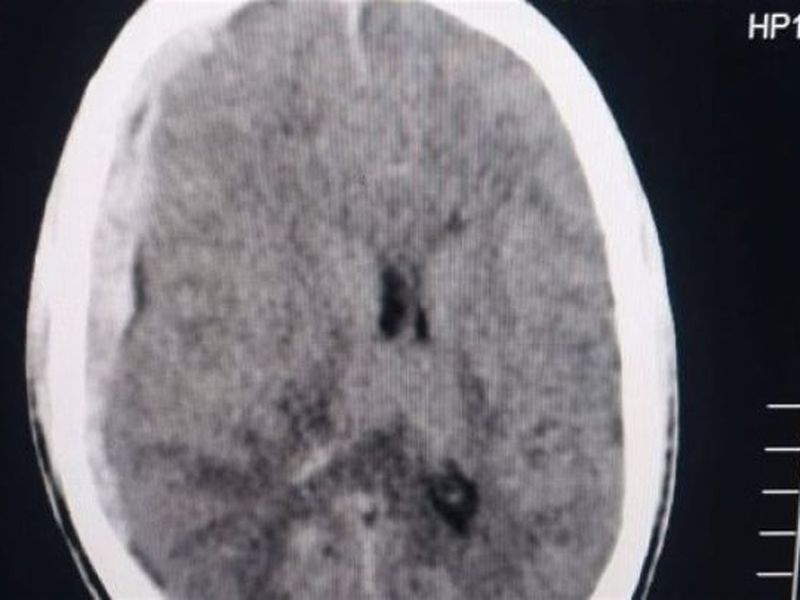

أعلنت مستشفى الأزهر الجامعي دمياط الجديدة حالة إنقاذ ناجحة داخل قسم الطوارئ ووحدة العناية المركزة بالطوارئ في إطار الدور الحيوي الذي

إنقاذ حياة شاب أصيب في رأسه بألة حادة في دمياط